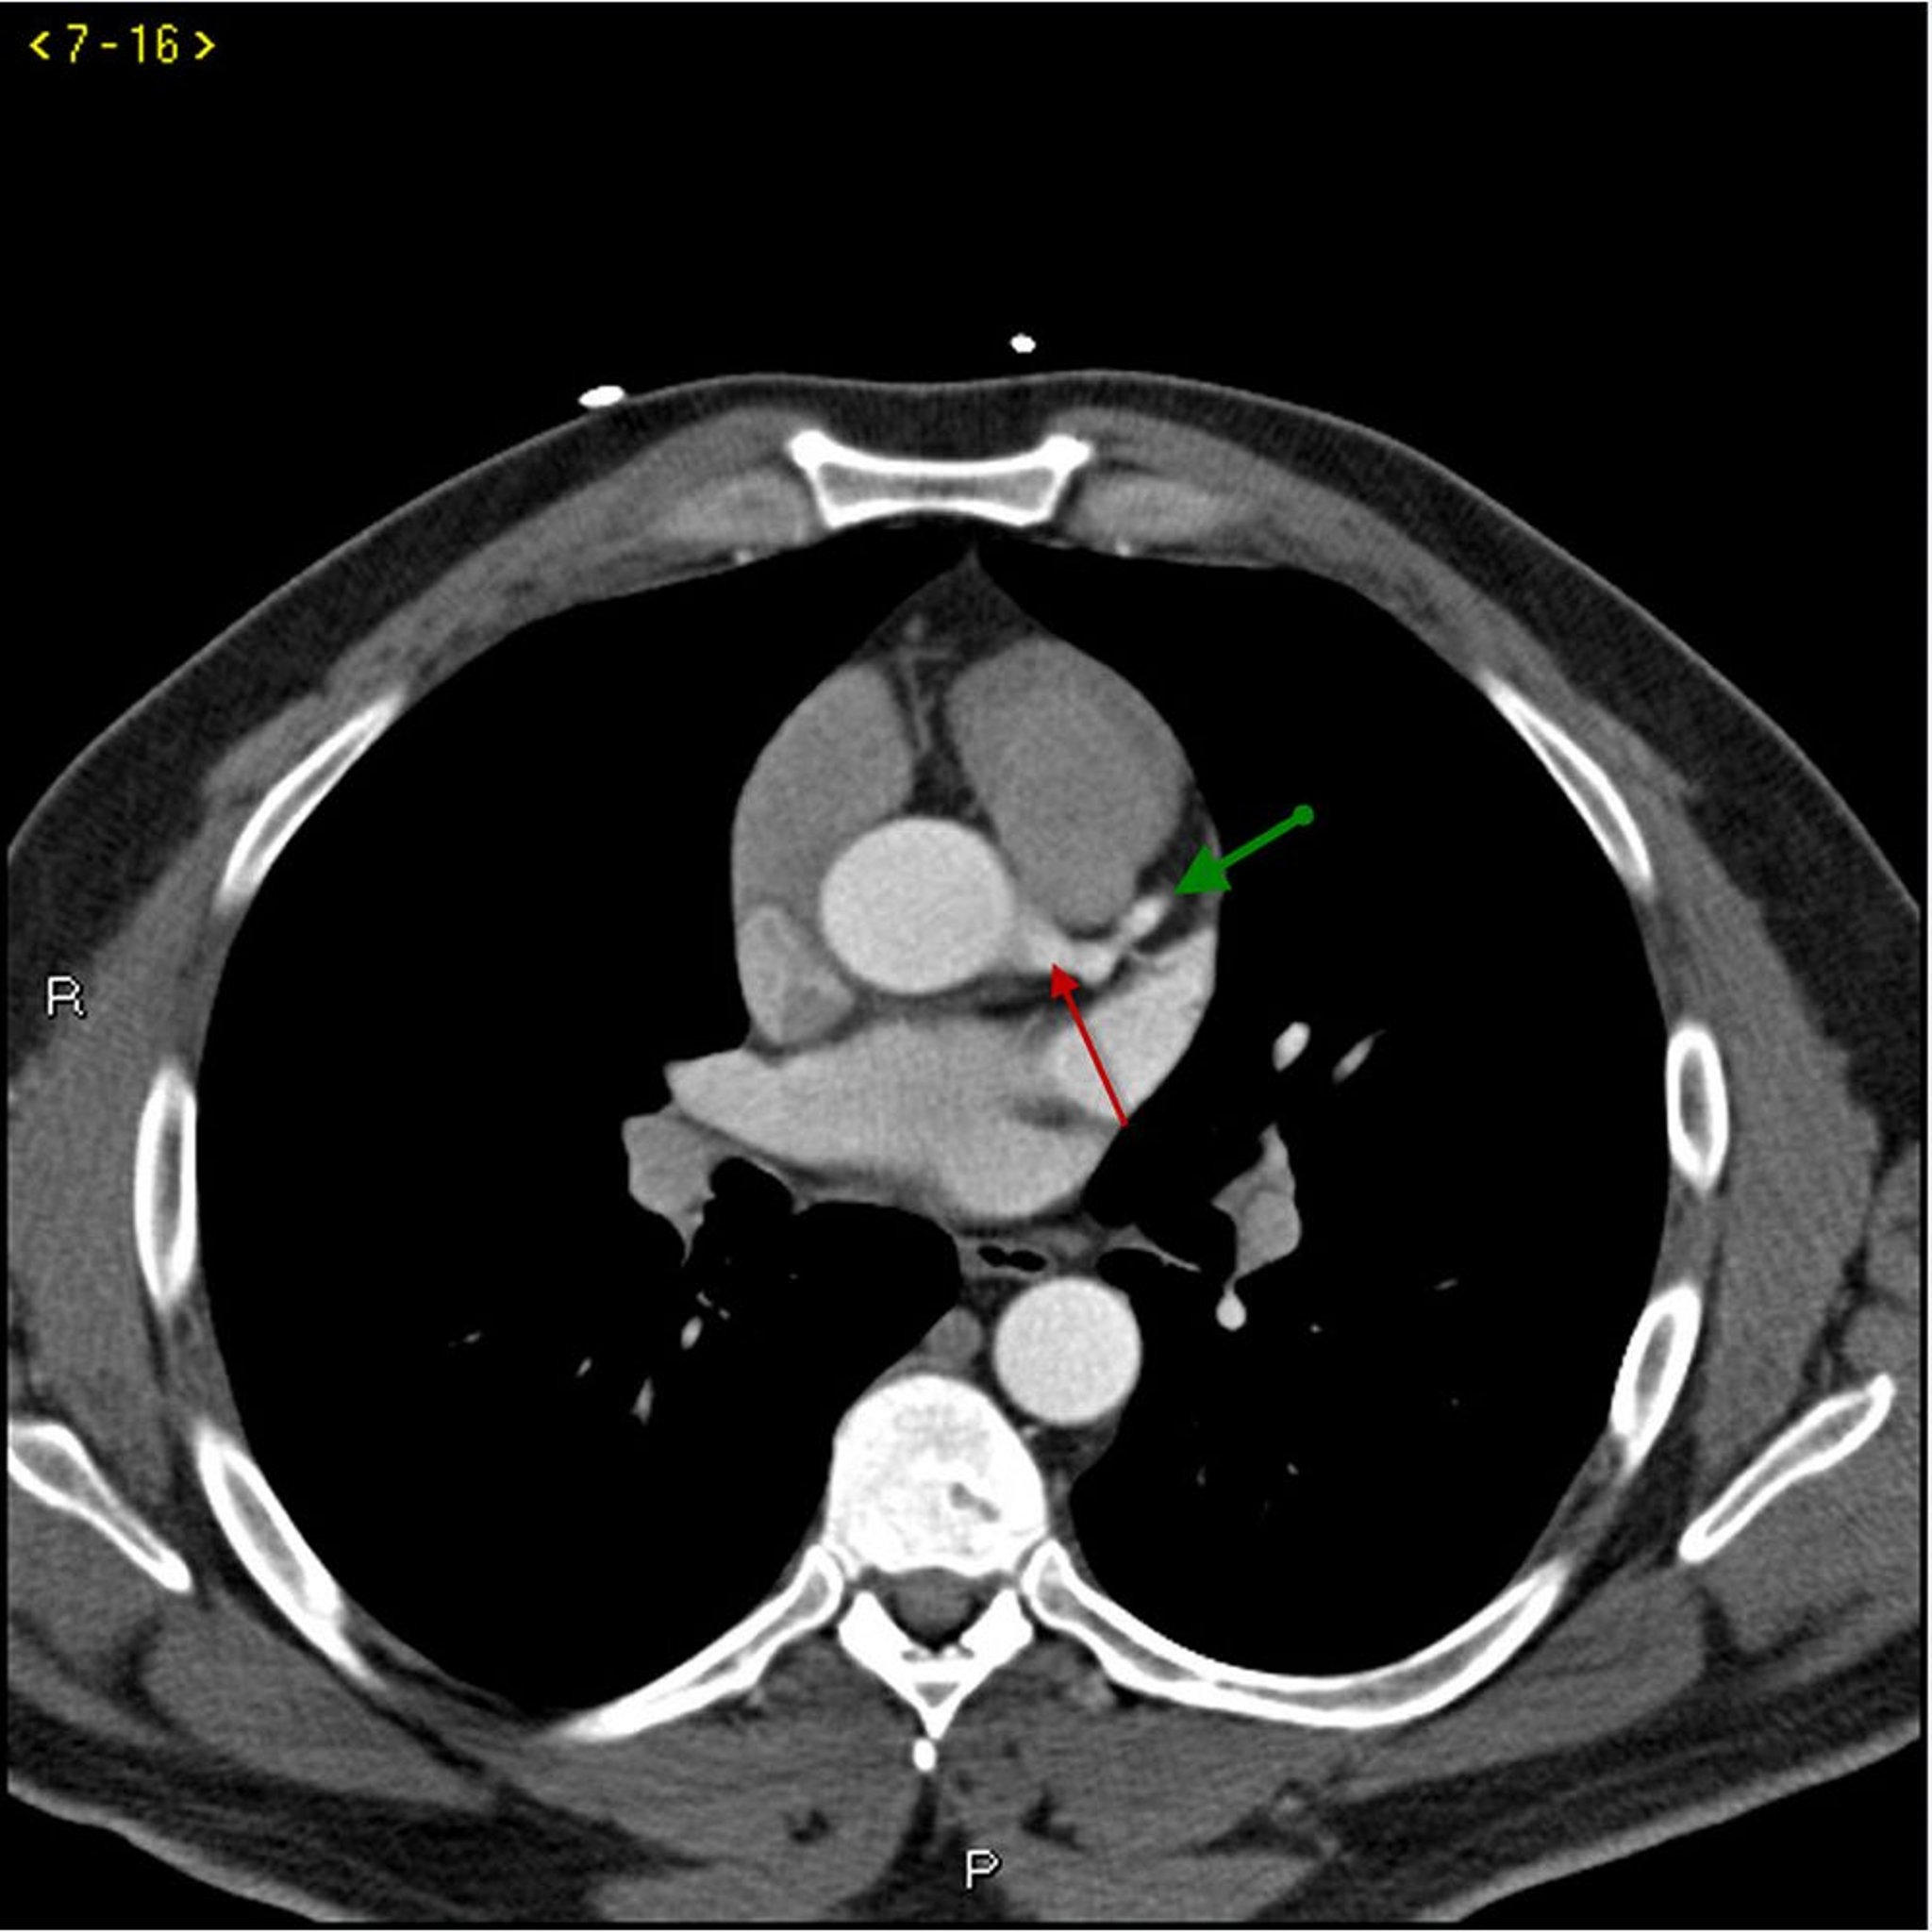

КТ с контрастированием, показывающая коронарные артерии в норме – слайд 1

КТ с контрастированием, показывающая коронарные артерии в норме Левая ветвь коронарной артерии обозначена красной стрелкой. Левая передняя нисходящая и левая огибающая артерии обозначены зеленой и синей стрелками соответственно, а правая коронарная артерия – филетовой стрелкой.